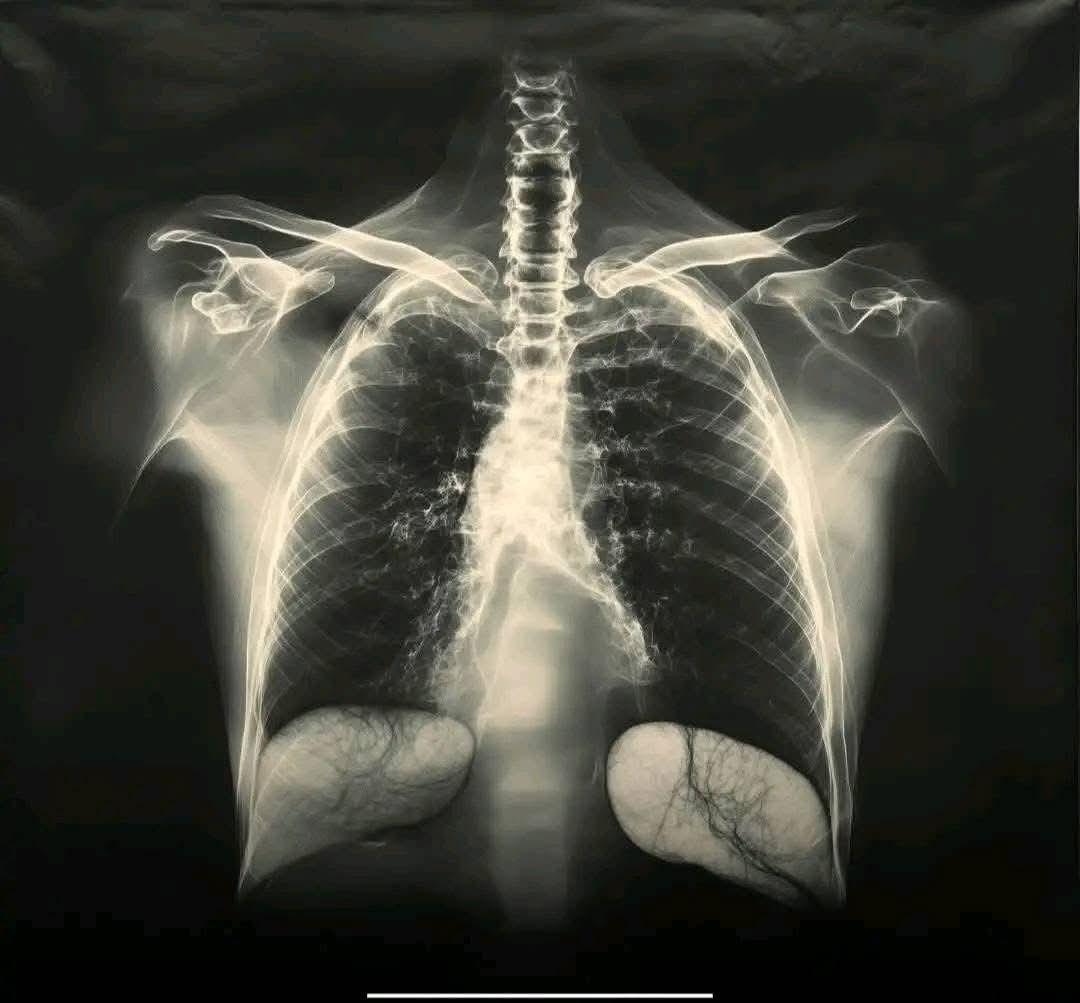

Vaccin contre la COVID et santé pulmonaire : ce que dit la science

Depuis le début des campagnes de vaccination contre la COVID-19, une question revient souvent : le vaccin peut-il nuire aux poumons ? Certaines personnes affirment ressentir un essoufflement ou une gêne respiratoire après leur injection. Ces inquiétudes méritent une explication claire, car la santé pulmonaire reste une préoccupation majeure depuis la pandémie.